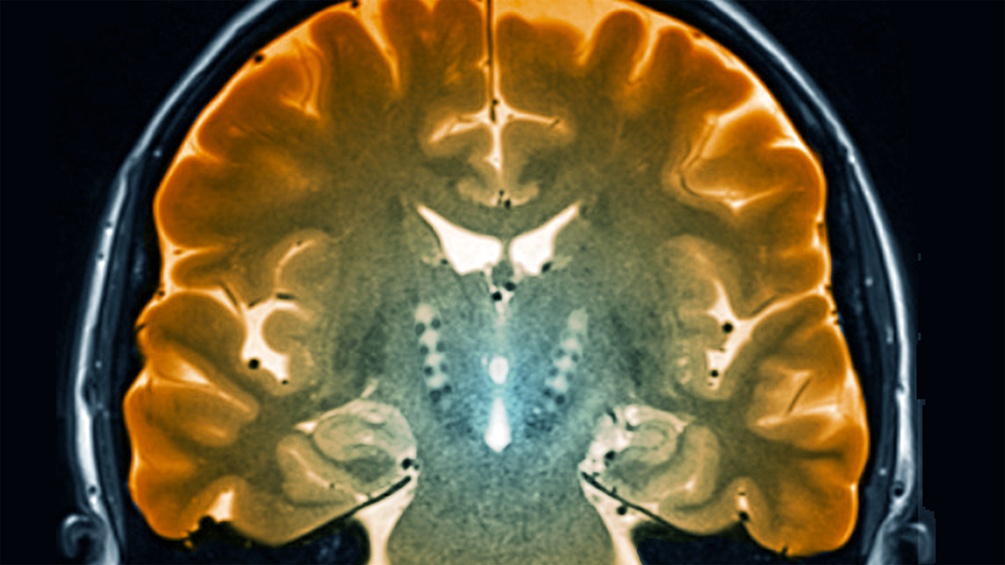

Am 11. April wird jährlich der Welt-Parkinson-Tag begangen, am Geburtstag des britischen Arztes James Parkinson, der vor über 200 Jahren die "Schüttellähmung" erstmals beschrieb: Eine chronisch fortschreitende Hirnerkrankung, bei der Nervenzellen absterben und ein Mangel des Botenstoffes Dopamin Zittern, Muskelsteifheit und Bewegungsverlangsamung verursacht. Eine nüchterne Beschreibung für die weltweit am schnellsten wachsende neurologische Erkrankung, deren vielfältige Symptomatik das Leben der Betroffenen tiefgreifend prägt.